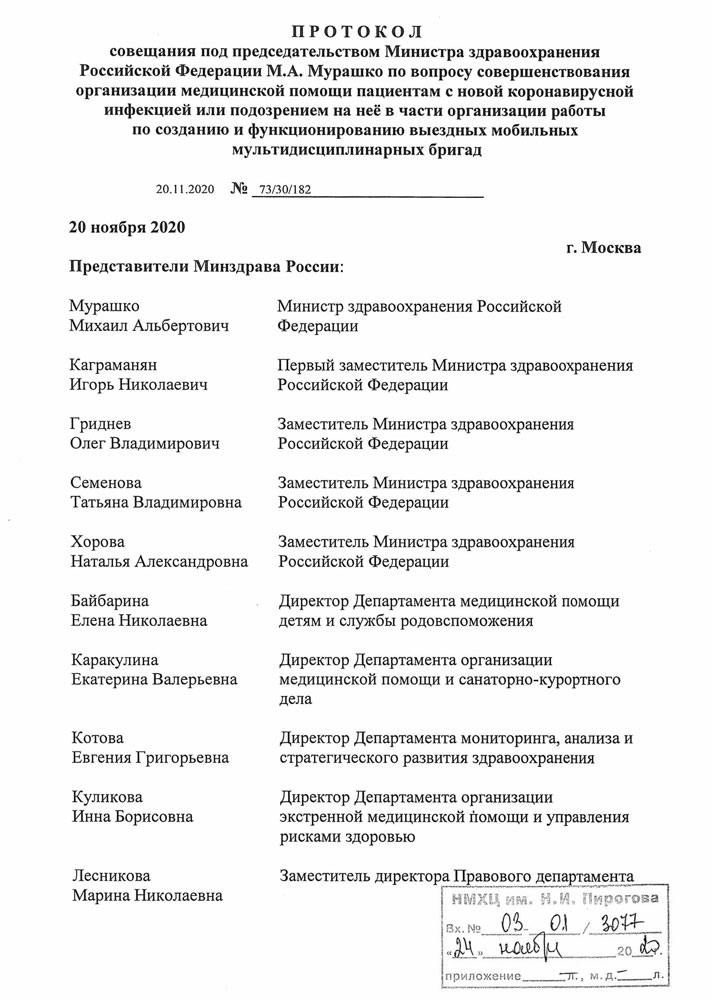

Пироговский Центр по поручению Министра здравоохранения РФ приступил к координационной работе по поддержке органов исполнительной власти субъектов РФ в сфере охраны здоровья и федеральных государственных медицинских организаций, подведомственных Минздраву России, при формировании выездных мобильных мультидисциплинарных бригад и организации их деятельности.